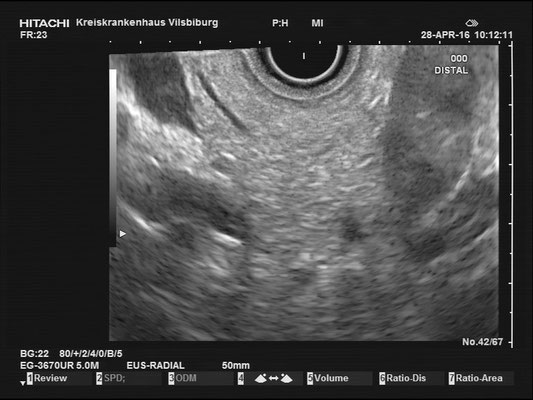

Pancreas

The images above depict a thorough inspection of the pancreas, as seen in an radial EUS Examination. We begin (hopefully ;) bei identifying the uncinate process between the golden V, which is formed by the aorta/V. cava and the mesenteric vessels. After spotting die usually hypoechoic ventral pancreatic root, the duodenal papilla can be identified (for a more detailed approach, please visit "Learning Endosono"). By following the splenic vein, the body and tail of the pancreas can be examined.

The most observant viewers will have noticed that not all images above depict normal findings but some abnormalities. (my bad ;)